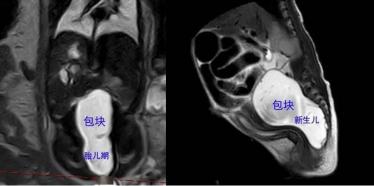

肖女士,在市妇幼保健院产检过程中发现胎儿腹膜后有个包块,并越长越大,分娩前核磁共振提示包块最大径线12cm,初步诊断为腹膜后肿瘤。由于腹膜后血管神经丰富,解剖结构复杂,对于血容量非常有限的新生儿来说,无疑是一个定时“炸弹”。医院立即组织多学科会诊,考虑胎儿内生型骶尾部畸胎瘤可能性大,并决定如果分娩后包块生长缓慢、不影响喂养和排便,则在度过新生儿期后,再考虑手术事宜。

然而事与愿违,宝宝出生后即出现尿潴留症状,开奶喂养即出现了肠梗阻,即喂养后,大小便不能正常排出。此时新生儿体重仅2900g,复查包块近12cm,如果出现骶前血管破裂出血,将是致命的。